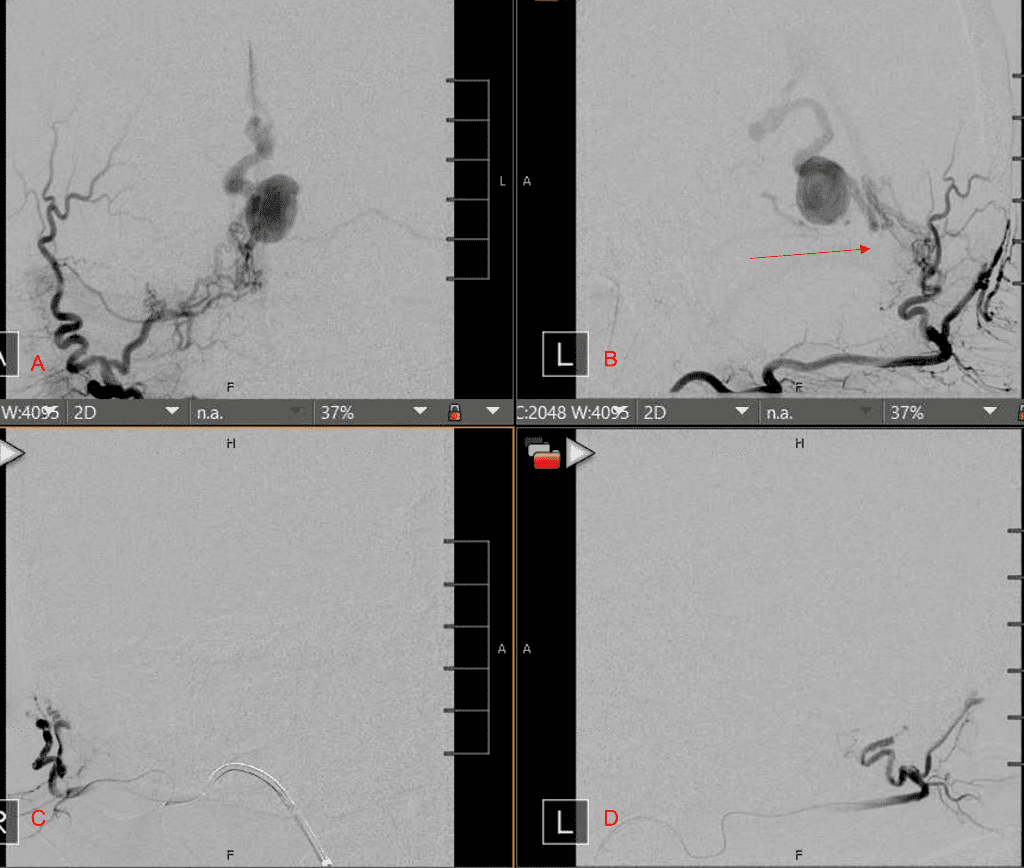

Figure 2. [A] Ruptured Varix/Aneurysm of the Deep Venous Posterior Fossa drainage and AV shunting (arrows) [B] Posterior Meningeal Artery Fistula [C] Right Middle Meningeal Artery Fistula [D] Post embolization Left Vertebral Angiogram demonstrates resolution of the high flow and pressure A-V Shunting following successful embolization with liquid embolic (NBCA).

Figure 3. Right ECA AP and Lateral angiograms Pre (A and B) and Post NBCA embolization (C and D) Demonstrate near complete obliteration of right Occipital and Middle Meningeal Artery Fistulas

Embolization was successful at immediately reducing the pressure into the Aneurysmal Varix with greater than 90% reduction in A-V shunts. After an intensive period of critical care monitoring and care for her initial brain hemorrhage, she made a near complete recovery with mild intermittent left sided paresthesias and generalized deconditioning. After receiving inpatient and outpatient Acute Rehabilitation, Physical, and Occupational therapy, she completely recovered all of her Activities of Daily Living (ADLs) at 3 months and achieved an modified Rankin Scale (mRS) of 0. On follow-up angiography, small residual low flow A-V shunts were identified and targeted for Gamma Knife Radiosurgery (Figure 5 and 6).